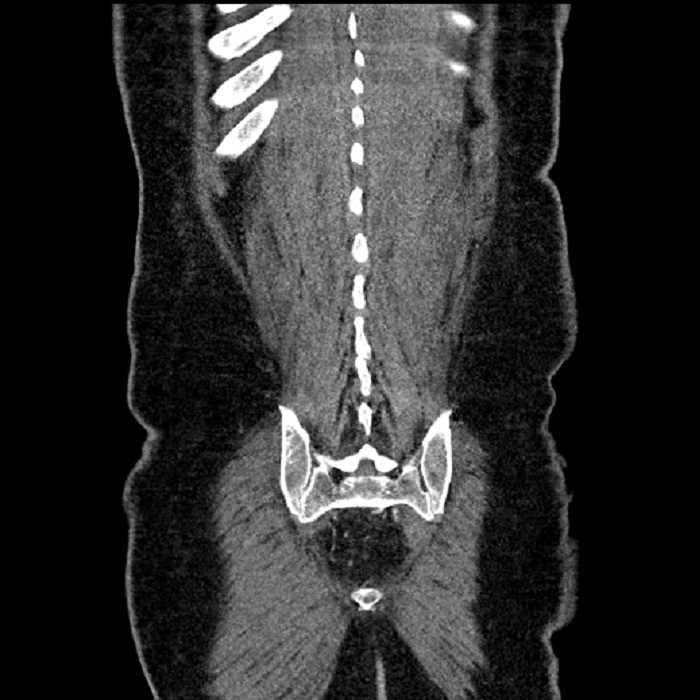

Age: 63

Sex: Male

Indication: Abdominal pain

• Large fluid density structure in hepatic segments 7 and 8 measuring 10 x 7 x 7 cm with internal septation and circumferential ill-defined low density compatible with edema

• Peripherally enhancing subcapsular collections along the anterior margin of the left hepatic lobe measuring 3 x 1 cm and 2 x 1 cm

• Clearly marginated fluid density structure in segment 7 and several other scattered tiny hypodensities, which likely represent cysts

• High grade stenosis of the left common iliac artery, with the left internal and external iliac arteries remaining patent

• Ankylosis of both sacroiliac joints

• Hepatic abscess

Acute sigmoid diverticulitis complicated by a small contained perforation and a large abscess in the right hepatic lobe. Additional small subcapsular abscesses along the anterior margin of the left hepatic lobe.

High grade stenosis of the left common iliac artery. The left external and internal iliac arteries are patent.

Hepatic abscess showing the double target sign with low density internally surrounded by a thin inner enhancing rim (red arrow) and ill-defined outer low density rim (yellow arrow). Blue arrow indicates an internal septation. Red arrows: additional smaller subcapsular abscesses. Red arrow: focal contained perforation associated with diverticulitis.